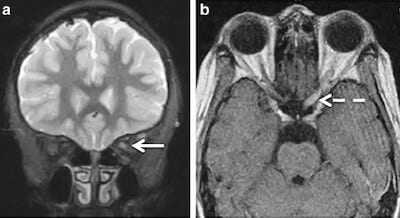

оптикомиелит девика мрт. симптомы и лечение оптикомиелит или болезнь девика серьезное аутоиммунное заболевание поражающее центральную нервную систему. особый вариант рс описан девиком devic в 1894 г. по данным мрт поражения спинного мозга носят больше некротический характер. хотя первоначально оптикомиелит считался монофазным заболеванием теперь очевидно что как и в случае рассеянного склероза болезнь девика это рецидивирующее заболевание 5.

мрт демиелинизация иммунопатология оптикомиелит рассеянный склероз subscribe posts from this journal демиелинизация tag. при проведении мрт спинного мозга можно оценить количество сегментов вовлеченных в патологический процесс. симптомы болезни прогноз продолжительности жизни клиническая. однако часто бывает что результаты мрт не позволяют различить эти состояния по этой причине nmosd часто принимаются за рс что может привести к ятрогении т.